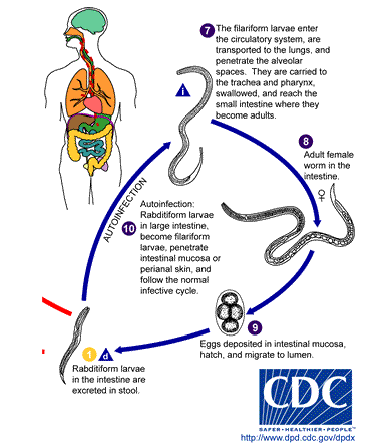

steps of s stercoralis life cycle

infective filariform larvae penetrate skin

autoinfection

filariform enter circulation or lungs where they are swallowed & enter small intestine

become adults in gut; adult female worm creates eggs in intestinal mucosa

eggs hatch into rhabditiform & develop into filariform & restart cycle

(strongyloides stercoralis) autoinfection life cycle

Eggs laid in gut hatch into rhabditiform larvae

Mature into filariform larvae

Penetrate intestine, migrate to lung

Asexual reproduction

Only female worms present

(strongyloides stercoralis) free living life cycle

Rhabditiform larvae mature into 4th stage larvae, then adults

Mate, lay eggs, hatch rhabditiform

Larvae mature into filariform larvae that mature into adults

Sexual reproduction

Occurs in temperate climates

(strongyloides stercoralis) parasitic life cycle

Rhabditiform larvae hatch from egg, mature into filariform larvae

Penetrate intact skin of human host

Moves into the auto-infective cycle from there

answer the followng abt s stercoralis:

What form is shed/acquired from the human?

If, an egg, is it embryonated or not?

If it is a larvae, what kind of larvae?

What hatches from the egg?

rhabditiform larvae in intestine are excreted in stool

eggs hatch into rhabditiform larvae after being fertilized by female worms in the environment or in the intestine

answer the following abt s stercoralis:

intermediate host? reservoir host?

What is the infective stage that gets back into the human?

How does the infective stage get back into the human?

General info about what happens once it gets back into the human.

Where do adults live?

intermediate: none ; reservoir: dogs/cats/humans

infective stage: filariform larvae

direct skin penetration

filariform go to lungs and are swallowed, reaching the small intestine where they become adults

adults live in large intestine